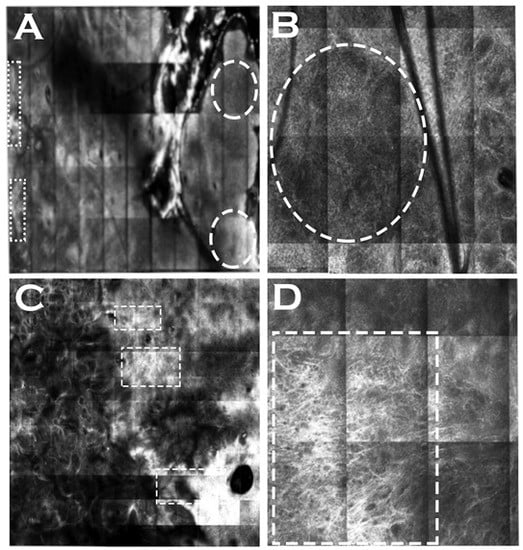

A study analyzed 108 cSCCs (62 in situ and 46 invasive) based on previously described histological criteria for SCC in reference to reflectance confocal microscopy, conventional OCT, and HD-OCT [80]. Under LC-OCT, the three key features of cSCCs were disarranged epithelial architecture, dyskeratotic keratinocytes, and atypical nuclei (Table 1) [80]. Identifying the DEJ was noted to be difficult in some lesions due to hyperkeratosis and acanthosis [80]. However, this study noted that an outlined DEJ without broad strands was visible in all situ cSCCs, but in only three invasive cSCCs (p < 0.001) when a DEJ was detected [80]. Non-outlined DEJ and broad strands were noted in invasive tumors [80]. Several other features were identified that discriminated cSCCs from normal skin, including hyperkeratosis, acanthosis, parakeratosis, erosion/ulceration, crowded nuclei, tumor-budding, and dilated vessels [80]. LC-OCT images of cSCC showed adnexal involvement by demonstrating an enlarged hair-follicle epithelium with nuclei of irregular shape and size [80]. Signs of solar elastosis were also present in the lesions [80]. Figure 6 highlights modes of LC-OCT and visible features of a biopsy-proven cSCC.

Figure 6. Line-field confocal optical coherence tomography (LC-OCT) features of squamous cell carcinoma. (A) Optical coherence tomography or en-coupe view showing ill-defined DEJ. (B) Confocal or en-face view highlighting atypical nuclei on left side and dermoscopic view on right side. (C) Three-dimensional view.